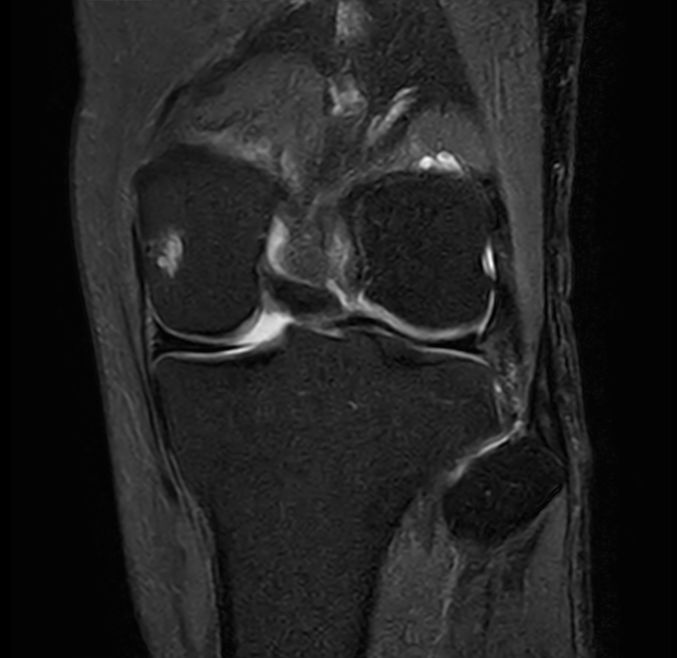

Coronal PDw TSE FatSat